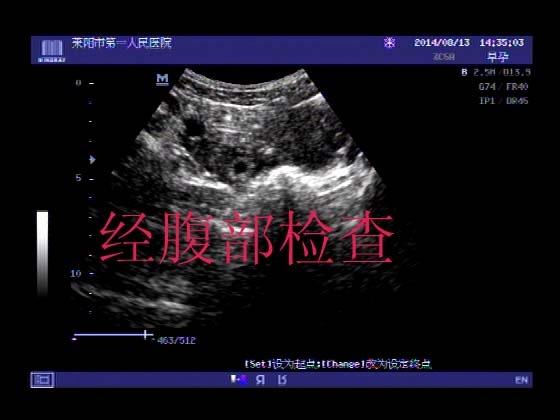

超声入门贴341:宫外孕(阴超的魅力)

女,32岁,停经15天,

一周前在上极医院检查:化验尿HCG阳性,血HCG400多,超声检查问见明显孕囊,让随访。